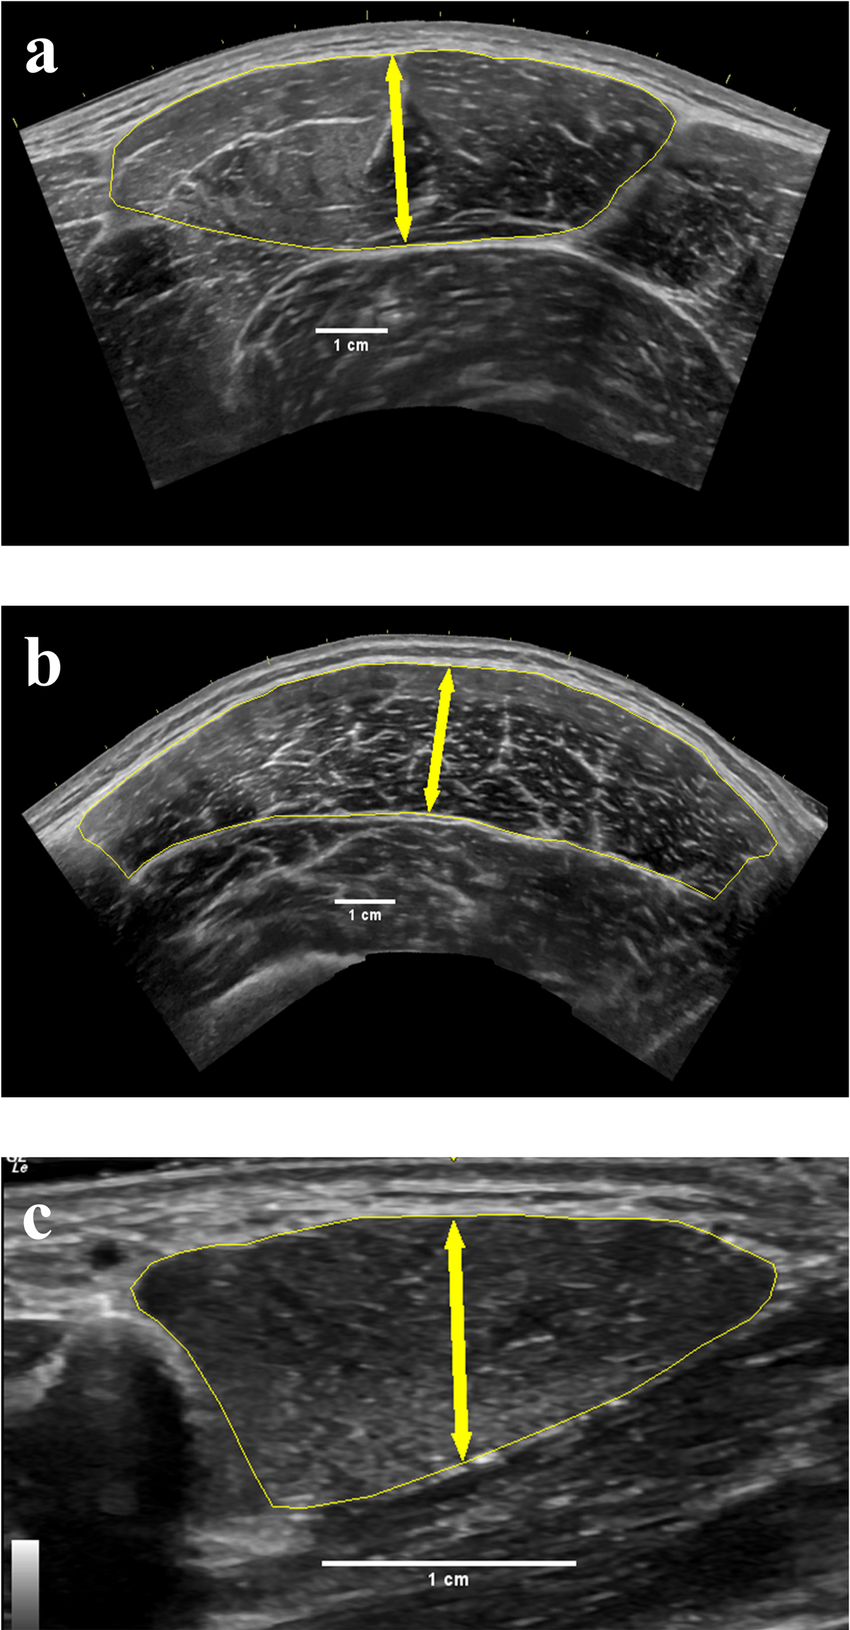

ultrasound: skeletal muscle

Hypoechoic fiber bundles interspersed with hyperechoic stromal connective tissue

ultrasound: fascia

Thin, hyperechoic (bright) structure

ultrasound: cortical bone

Hyperechoic (bright) linear line with posterior acoustic shadowing due to complete reflect

(high density of molecules, with hard material properties)

ultrasound: cyst

anechoic

ultrasound: nerve

'Honey-comb' appearance in transverse view; 'train track' in longitudinal view

ultrasound: articular cartilage

Anechoic (black) layer overlying the periosteum

ultrasound: tendon

comprise multiple individual, longitudinally oriented, parallel collagen fibers that are tightly bundled, resulting in a fibrillary pattern on ultrasound

This results in the characteristic hyperechoic appearance of tendons when the US beam is oriented 90 degrees to the tendon